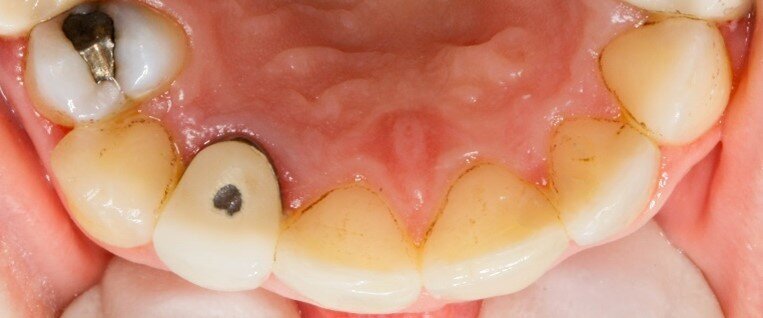

La prima paziente è una donna di anni 33 che gode di buona salute generale, non assume farmaci e non è una fumatrice. All’esame obiettivo si notano diverse otturazioni in amalgama, corone protesiche e un impianto osteointegrato ma non emergono problemi particolari, eccetto delle black stains di cui la paziente lamenta la presenza. Si procede con la raccolta della documentazione fotografica, la rilevazione dell’indice di placca attraverso l’utilizzo del rivelatore di placca e la compilazione della cartella parodontale. Dall’analisi dei dati raccolti non emergono problematiche parodontali, ma è da notare quanto l’igiene domiciliare sia insufficiente (IP=69%). Vengono raccolti in una tabella riassuntiva anche i dati relativi alla presenza di black stains. Si prosegue con la motivazione e l’istruzione ad un’accurata igiene orale domiciliare e si invita la paziente a tornare una decina di giorni dopo per sottoporsi ad una seduta di igiene orale professionale. La paziente ha dimostrato una buona adherence rispetto ai consigli di igiene che le sono stati dati, il livello di igiene orale è notevolmente migliorato e si decide per un richiamo di igiene semestrale. Dopo aver effettuato la seduta di igiene professionale si chiede alla paziente di cambiare testina allo spazzolino elettrico in uso e di assumere “Lautoselle” una volta al giorno per i tre mesi successivi. La paziente viene controllata dopo un mese e quindi al termine del periodo di assunzione del probiotico, vengono nuovamente scattate delle fotografie e compilata la tabella riassuntiva per monitorare la formazione delle black stains. Infine, lo stesso tipo di controllo viene effettuato dopo altri tre mesi, cioè a distanza di sei mesi dalla seduta di igiene orale e quindi dalla rimozione delle black stains; successivamente è stata effettuata la seduta di mantenimento di igiene.

A distanza di sei mesi dalla rimozione dei pigmenti durante la seduta di igiene orale professionale, i siti che presentano black stains sono diminuiti del 53,13%. I pigmenti inoltre hanno iniziato a ripresentarsi, seppur in quantità ridotte, a due mesi dalla seduta di igiene, mentre solitamente la ricomparsa avveniva a distanza di 3-4 settimane (Figg. 4a-4c).

Fig. 4a - Fotografia del secondo sestante palatale al primo rilevo delle black stains.

Fig. 4b - Controllo a tre mesi.

Fig. 4c - Controllo a sei mesi.